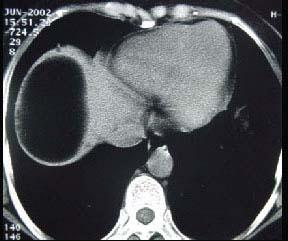

男,30岁,右下腹稍隆起,CT检查如图,最可能的诊断为 ( )A.右膈下脓肿B.间位结肠C.右膈下脂肪瘤D.右下肺肺大疱E.右下肺炎

问题 男,30岁,右下腹稍隆起,CT检查如图,最可能的诊断为 ( )

选项 A.右膈下脓肿 B.间位结肠 C.右膈下脂肪瘤 D.右下肺肺大疱 E.右下肺炎

答案 C